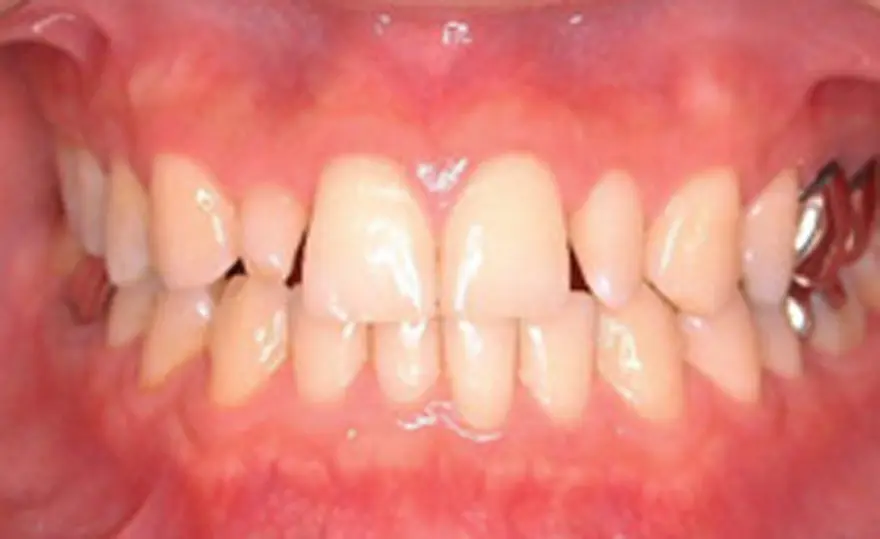

MTM(部分的な矯正)治療例4

矮小歯のあるケース

| 患者さまの年齢・性別 | 20代・男性 |

|---|---|

| 治療期間 | 5ヵ月 |

| 治療費(税込) | 242,000円 |

| 主訴 | 前歯の隙間が気になる。 |

| 診断名・主な症状 | 真ん中のスペースの閉鎖と右の矮小歯が裏側になってしまっている。 |

| 治療に用いた主な装置 | セルフライゲーションブラケット装置(デイモンシステム) |

| 治療内容 | 前歯の隙間を閉じ、右の裏側にある歯を前方に移動させています。上顎左右の前歯の隣の歯が矮小歯と言う本来より小さい歯のため、このままでは再度隙間があいてくる可能性があります。矯正治療後、この歯を少し大きくする治療が必要となります。 |

| 抜歯部位 | 非抜歯 |

| 通院回数・メンテナンス頻度 | 5回 |